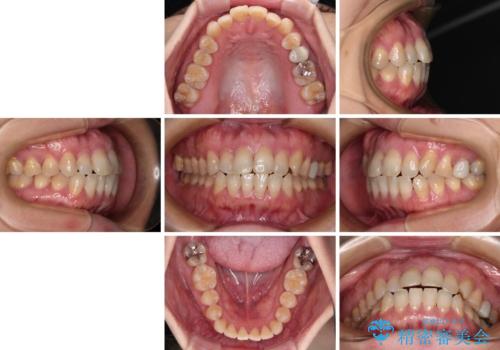

- 前歯のデコボコと口元の突出感を気にして来院された患者様です。

上下前歯がくちばしのように突出していたため、上下左右の第一小臼歯4本を抜歯し、ワイヤー装置にて矯正治療を行うこととしました。

上顎骨に対して下顎骨がやや前方位に位置しているため、歯肉退縮を回避するために下顎前歯をあまり内側に移動させることができない状況でしたが、十分に口元の突出感を改善することができました。